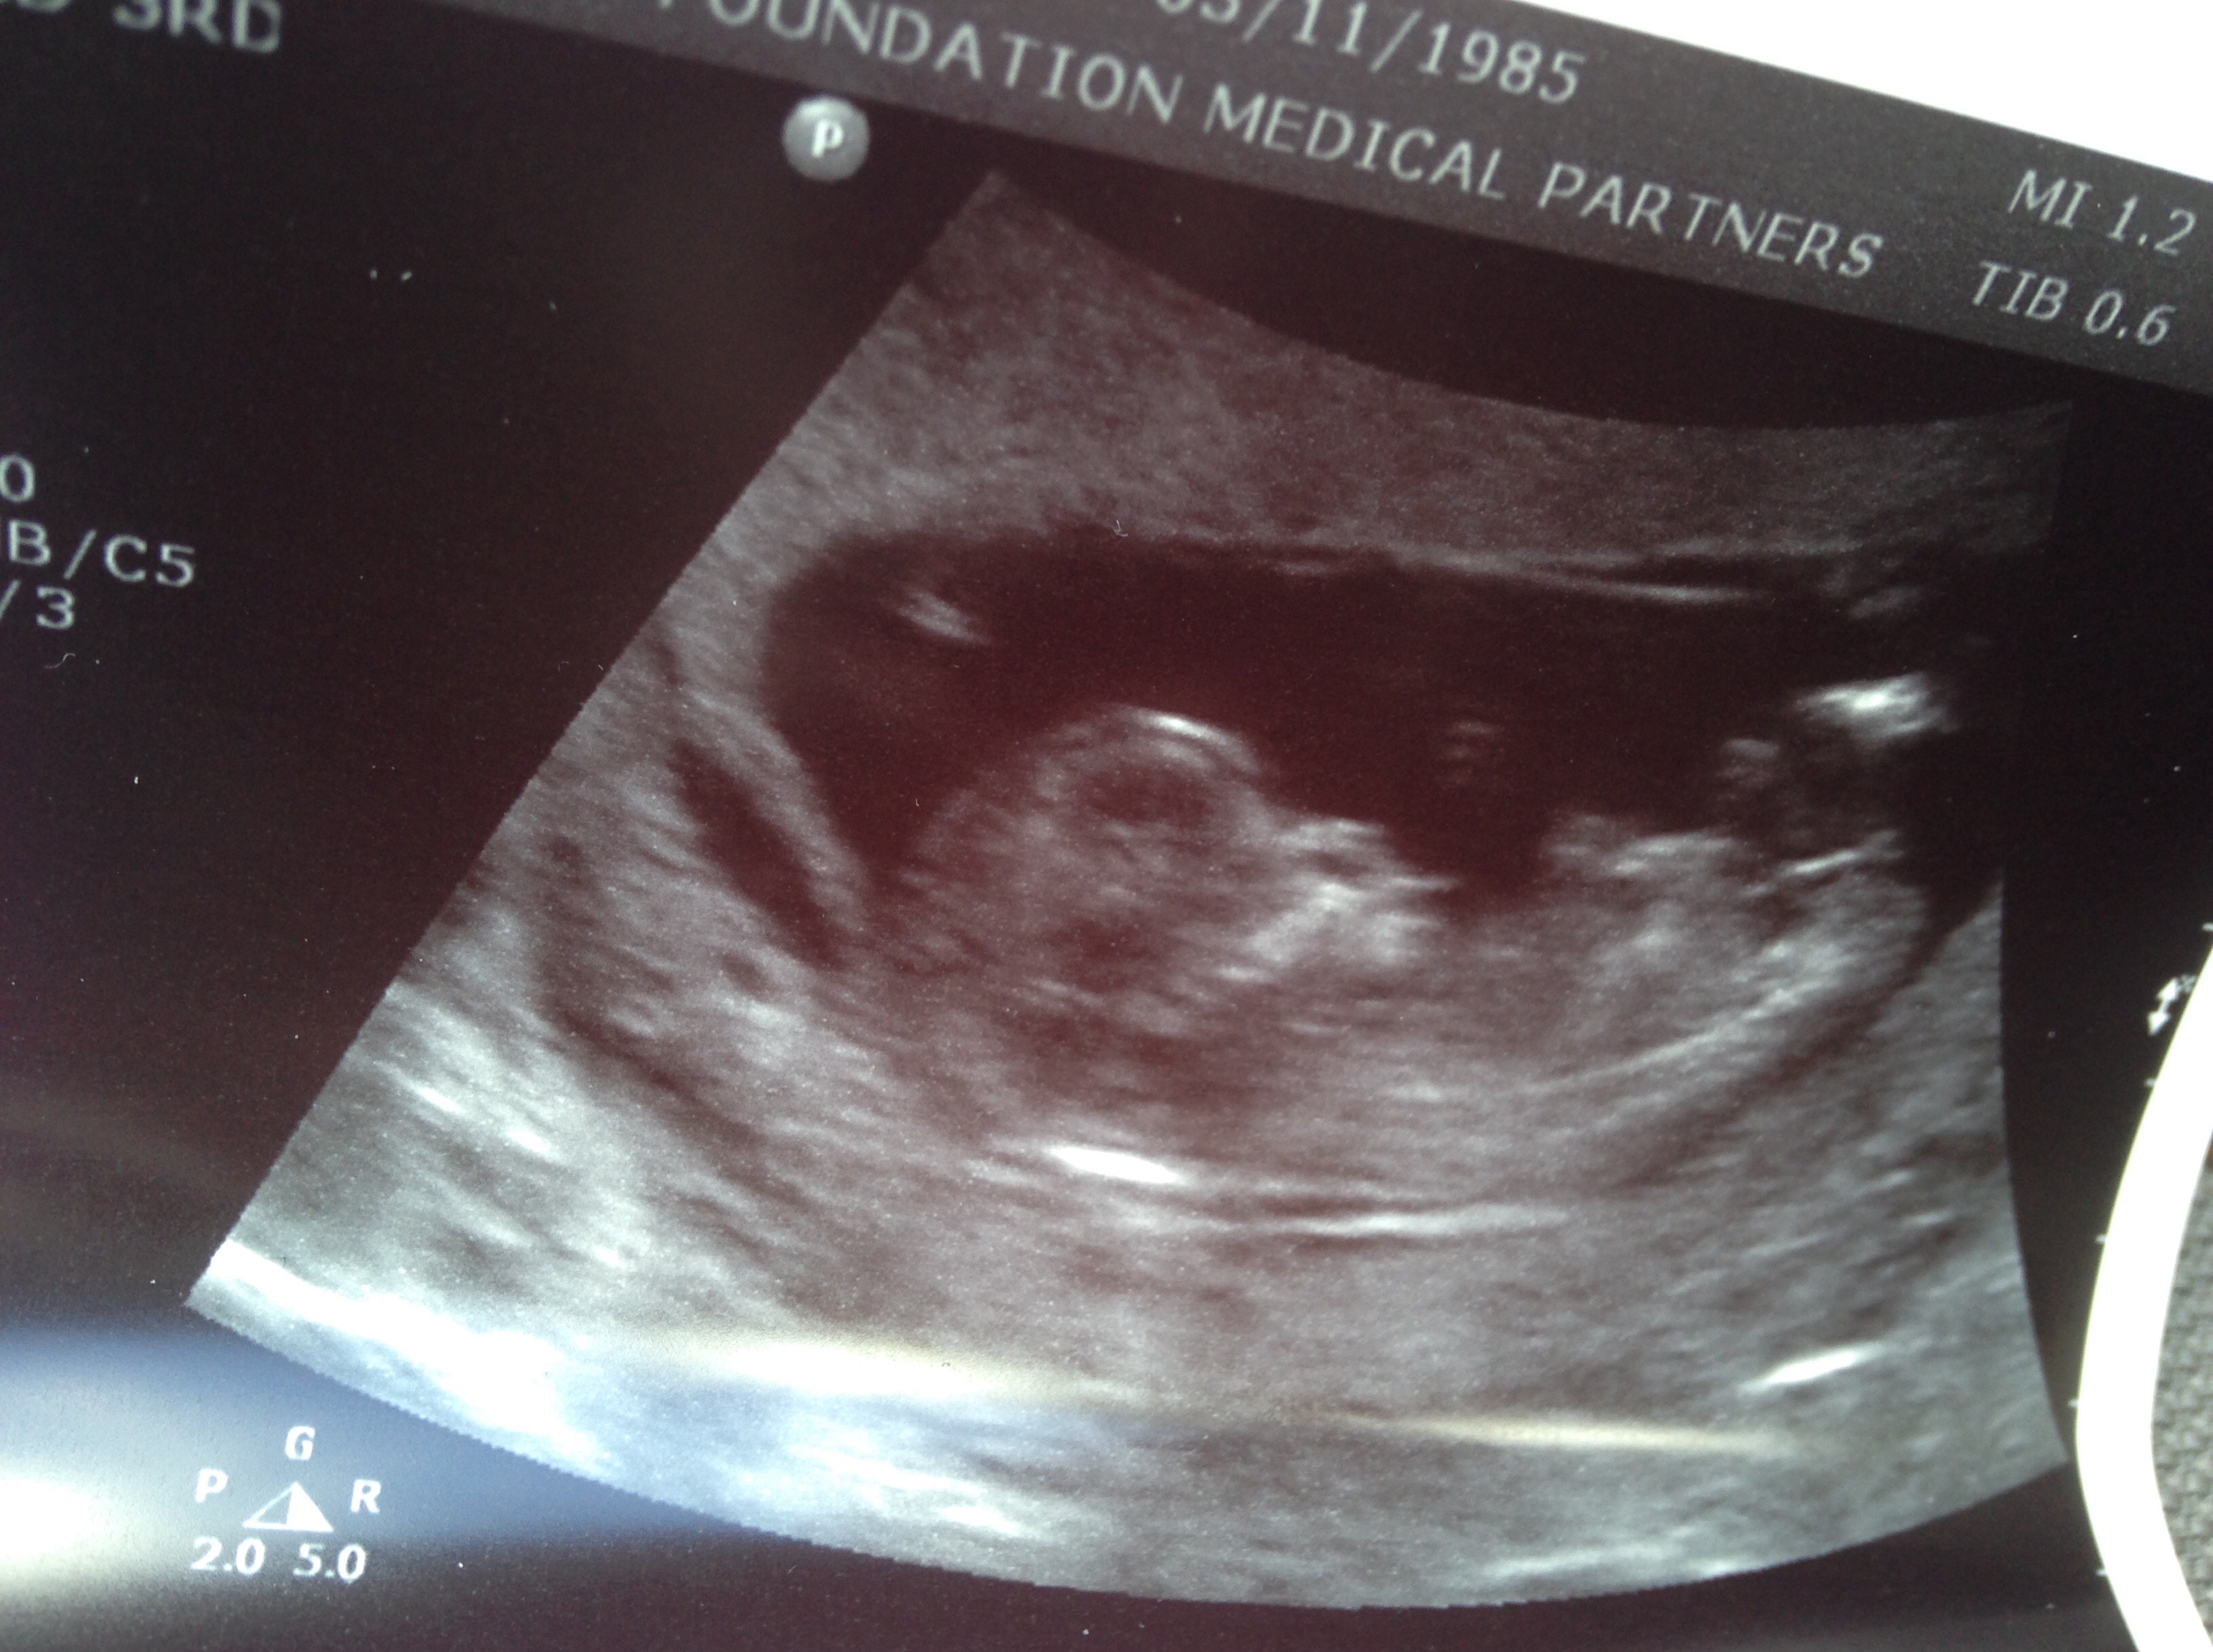

Not sure if you can tell from these but I'm curious.

12w6d

Then I'd say girl :)

You will get lots more guesses I'm not an expert on nubs but you have nice clear nubs there :)

girl

Girl!

Leaning girl too